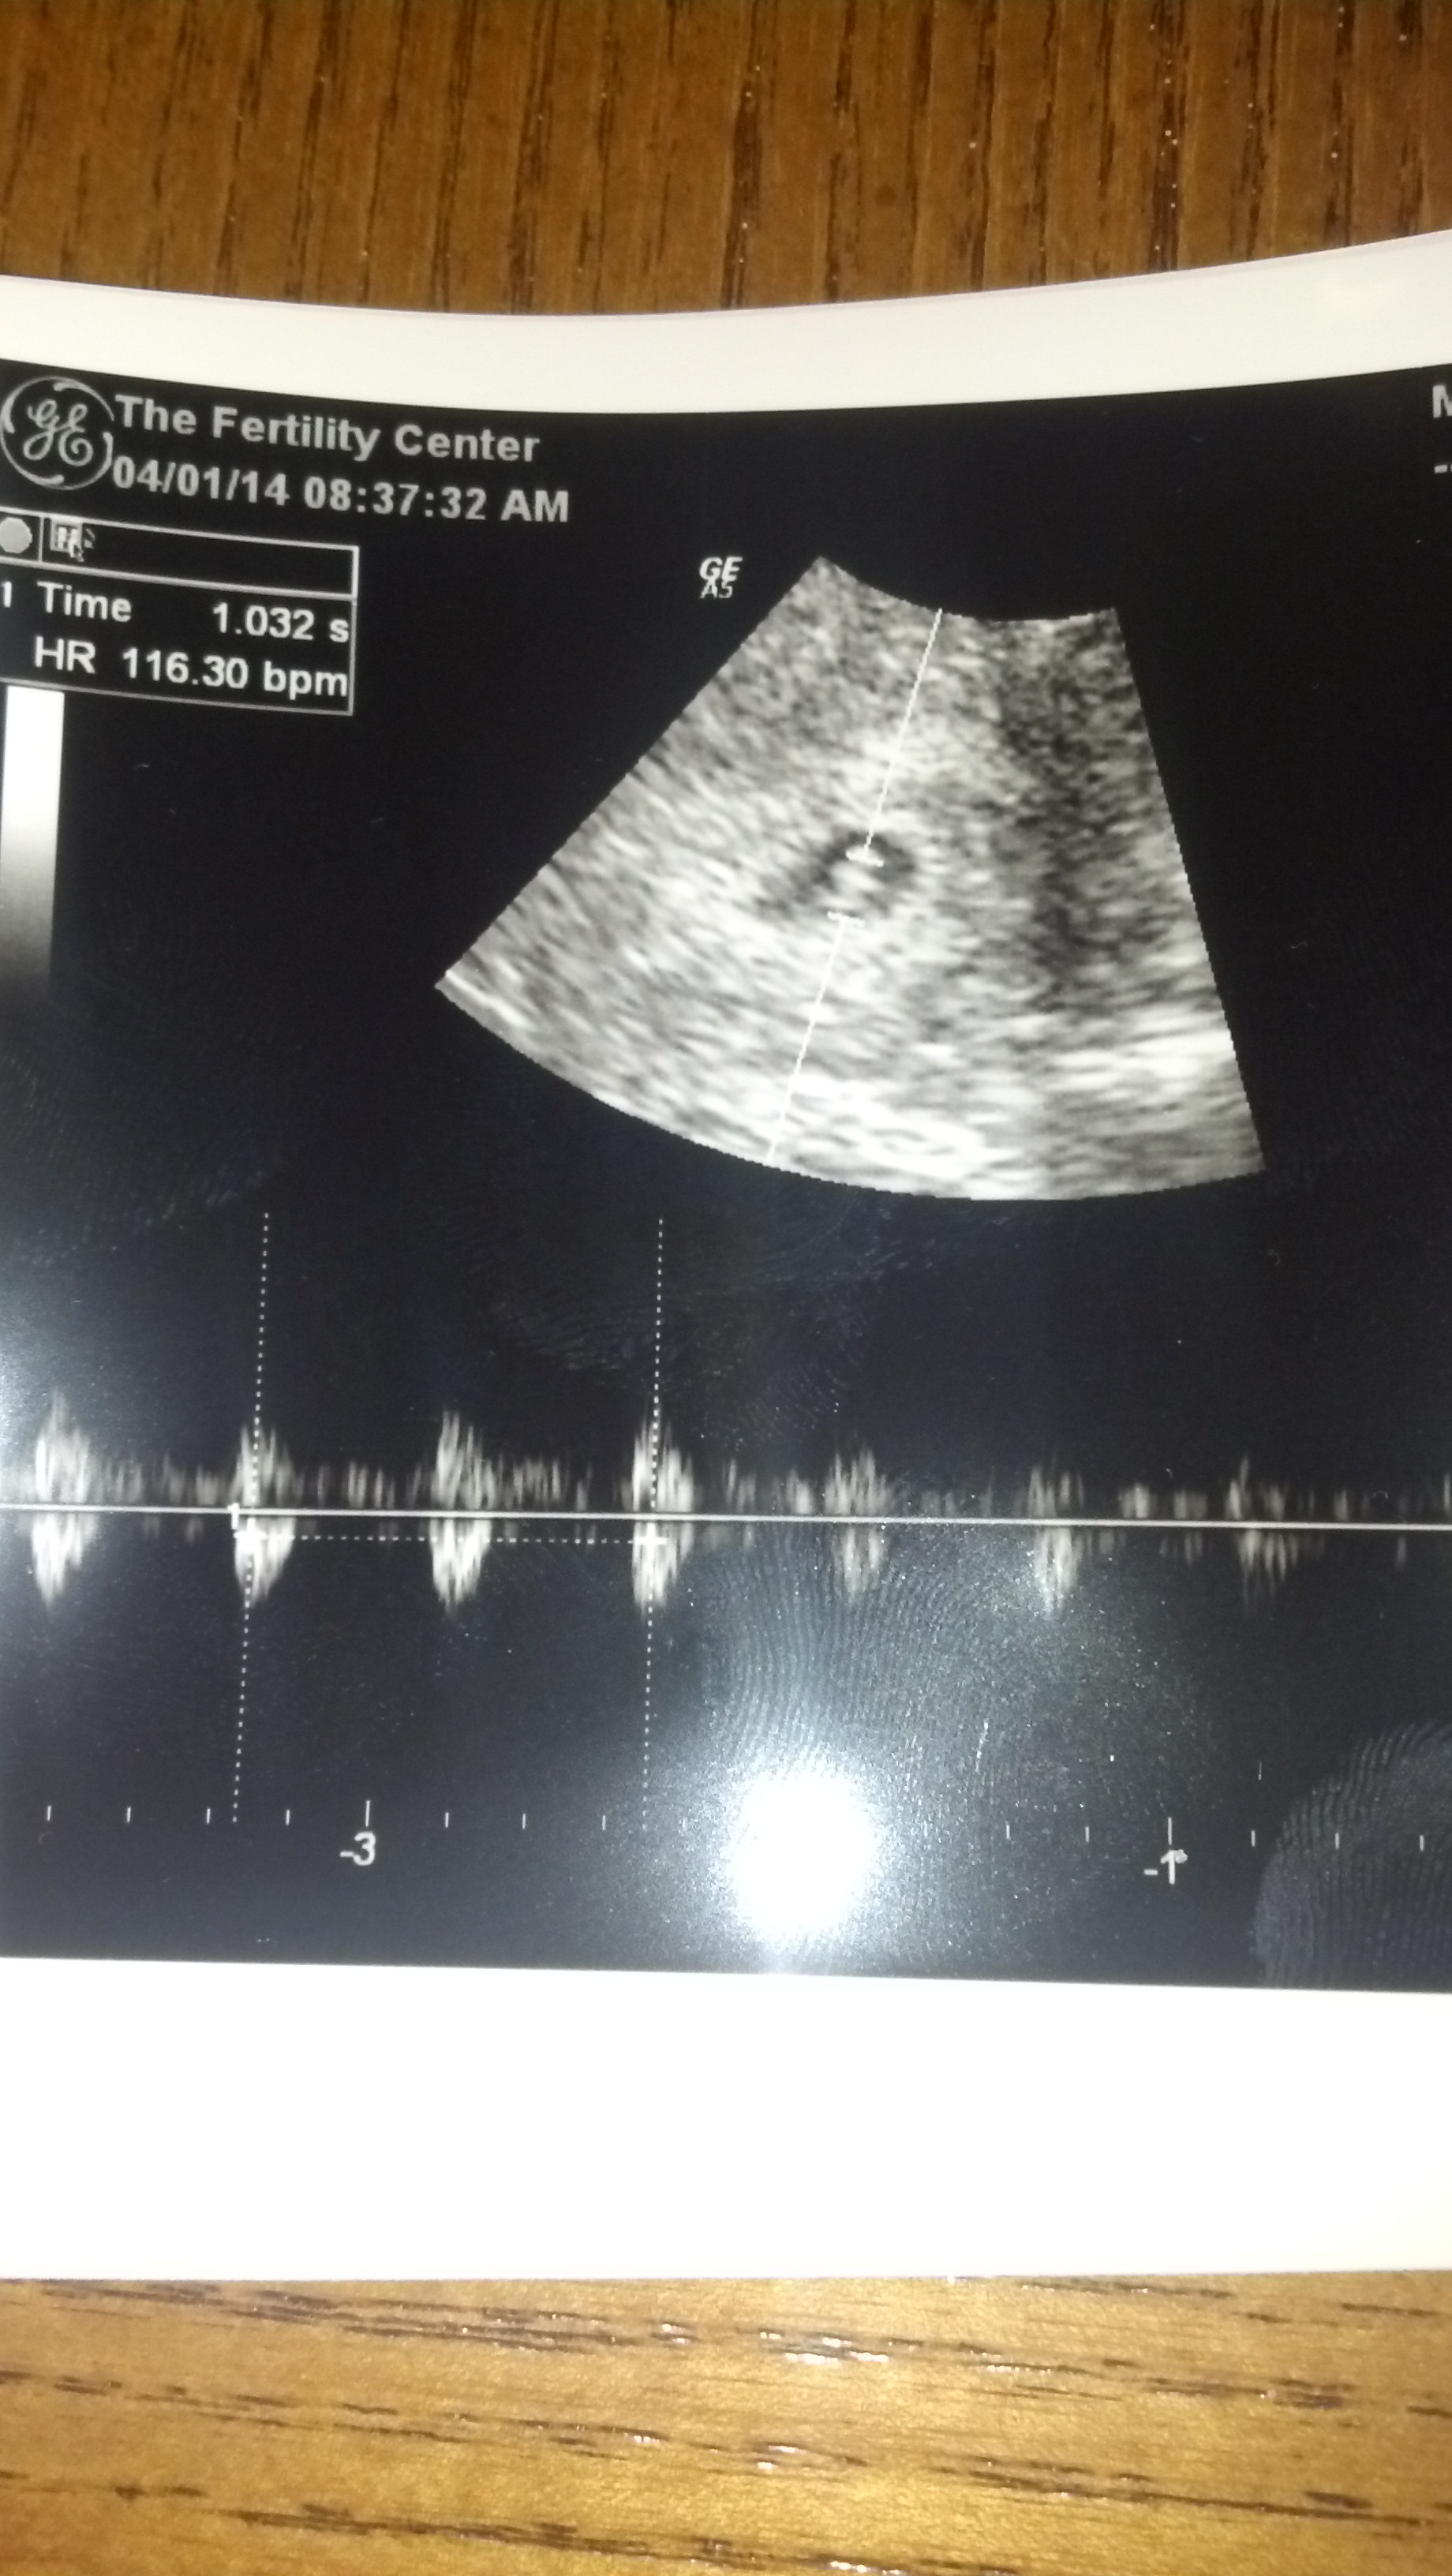

Baby last week at 6 wk 6 days.